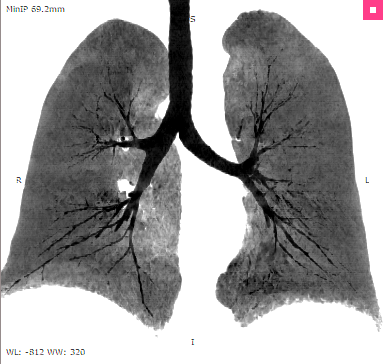

MinIP |

•MinIP (Minimum Intensity Projection)